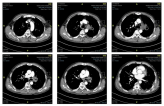

胸部CT:显示左肺上叶病变伴空洞,左肺门肿大。

胸部增强CT:提示左肺门淋巴结肿大。